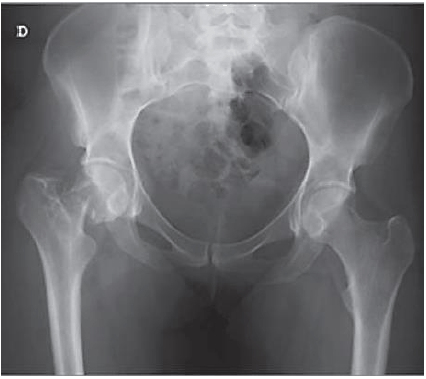

A imagem abaixo se refere a:

Provas